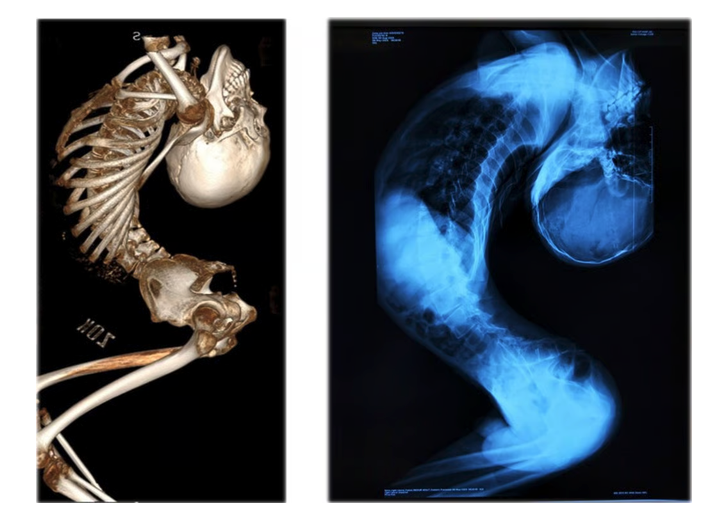

180도로 꺾인 허리로 인해 '폴더 소년'으로 불리던 중국의 장옌천이 마침내 똑바로 서는 데 성공했다. 지난 25일 홍콩 매체 사우스차이나모닝포스트(SCMP)는 장옌천이 최근 진행한 생중계에서 처음으로 곧게 선 채 걸음을 내디뎠다. 중국 산둥성의 작은 마을에서 자란 그는 목이 점점 뒤로 꺾이며 몸이 알파벳 'Z'자 형태로 접혀 갔다. 곧게 서려 해도 키는 120㎝에 불과했고, 자연스럽게 서 있으면 80㎝ 정도에 그쳤다.

2024년부터 장옌천은 척추 기형 치료로 유명한 량이젠 교수의 치료를 받기 시작했고, 올해 6월 마지막 수술을 마쳤다. 그는 지난 2년간 허리뼈, 경추, 고관절, 흉부 뼈를 절단 후 재정렬하는 네 차례의 초고난도 수술을 받았다. 전신 마비나 사망 위험이 따르는 극도로 위험한 수술이었지만 성공적으로 끝나 그는 곧바로 침대에 똑바로 누울 수 있었다. 의료진은 이를 "세계 최초의 180도 척추 교정 수술 성공 사례"라고 발표했다.